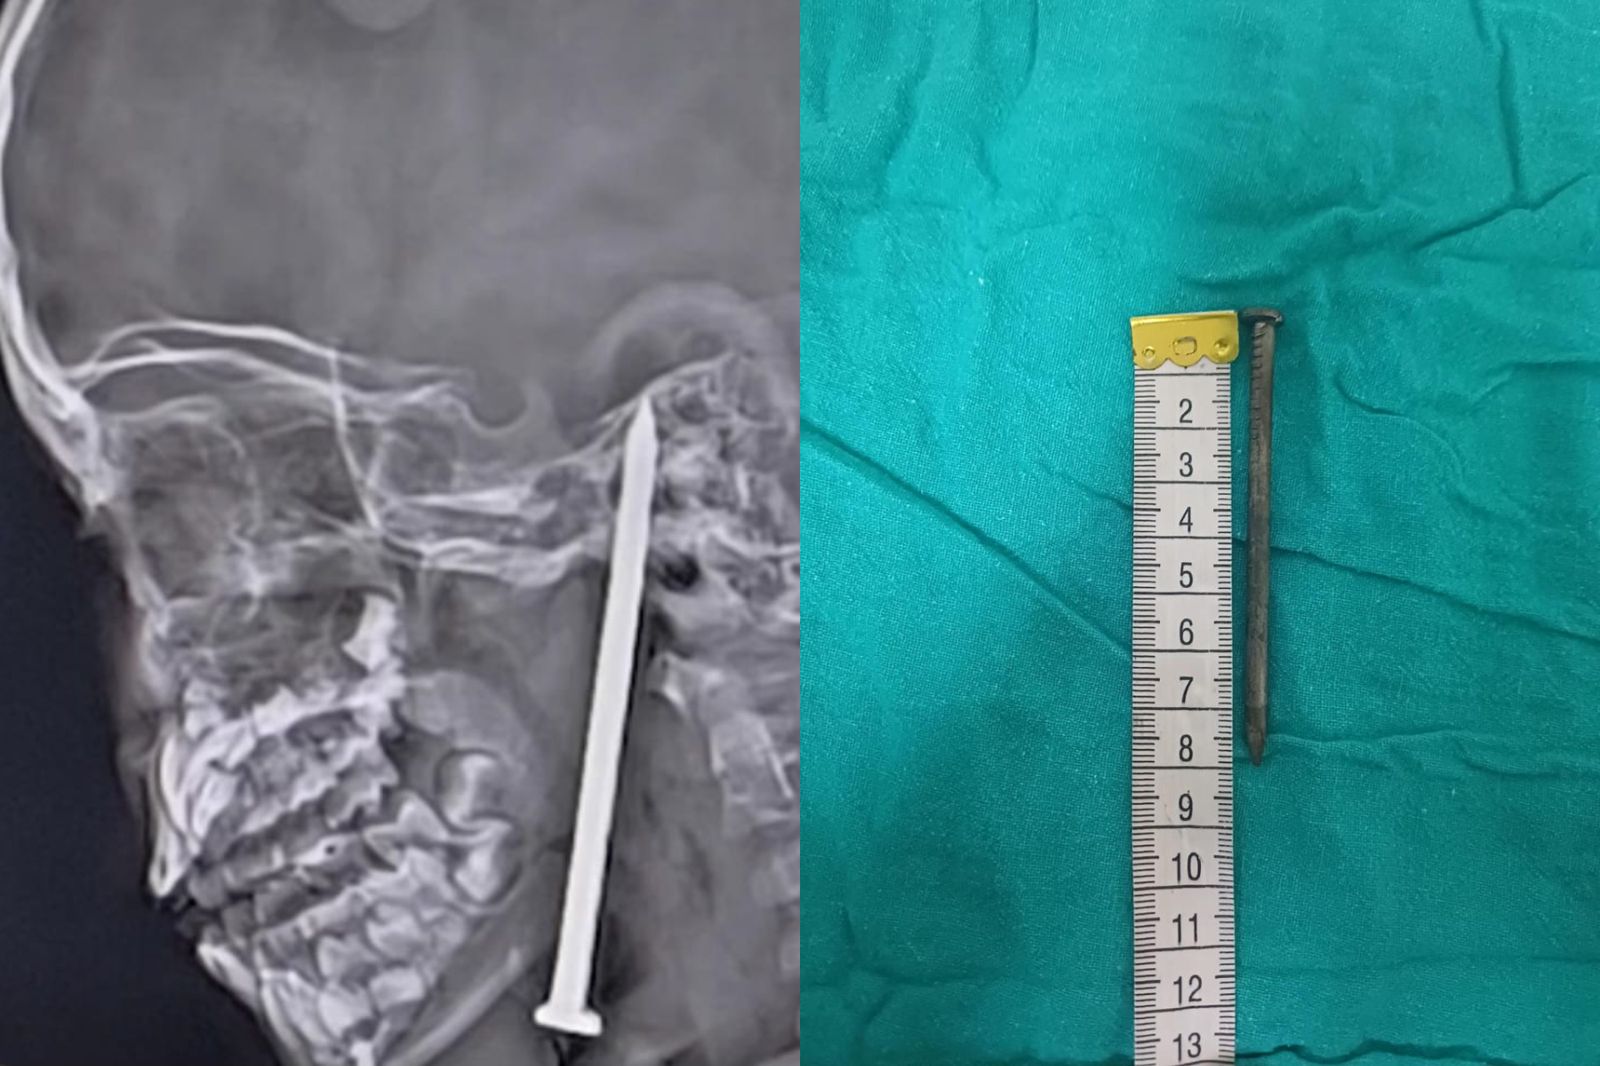

超恐怖!印度一名7歲男童在玩耍過程中不慎跌倒,結果一根長8公分的鐵釘插進男童的頸部,並刺進他的腦部,隨後被緊急送往醫院進行手術,所幸手術成功,不僅順利將釘子取出也沒有損傷任何重要血管。醫師表示,釘子已經插進腦部,一個小小的失誤就有可能會致命。

據今日印度報導,一名巴爾拉姆普爾縣(Balrampur)的7歲男童,在玩耍時不小心跌倒,結果一根8公分的鐵釘刺進男童的脖子,並進入腦部,他被緊急送往附近的醫院,不過由於傷勢嚴重,就被轉至勒克瑙國王喬治醫科大學(KGMU),在掃描核磁共振跟CT報告後,要替男童進行手術治療。

不過,醫師們意識到這起手術極為危險,並立即組建了由神經外科、耳鼻喉科、麻醉科、創傷科和兒科專家組成的手術團隊。手術團隊利用顯微外科技術以及神經手術導航系統,順利將男童腦內的釘子取出,並沒有傷及任何重要血管。醫師表示,釘子已經進入到腦部,即便是發生一個小失誤,也可能會致命。

經過10個小時複雜的手術後,男童被送往加護病房觀察,此後他的病情逐漸好轉,並且已經脫離生命危險,正在逐漸恢復健康當中。KGMU的醫務總監表示,這起病例將被記錄下來,作為對醫學的巨大貢獻,手術的結果將會發表在國際期刊上,為全球醫學界提供見解。